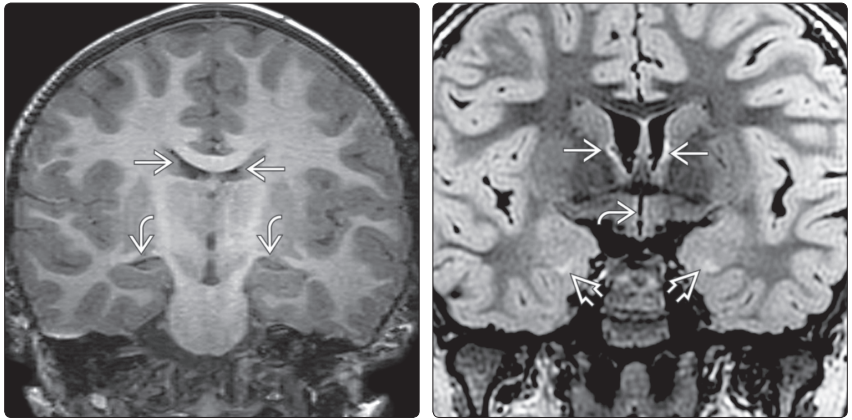

(左图)MR冠状位T;WI示(侧脑室体部→和枕角水平↪):颞角呈裂隙状,位于海马内侧喙缘(rostralto the medial aspects of the hippocampi)。(右图)冠状位FLAIR MRI示:正常儿童三脑室↪,呈裂隙状。正常额角→狭窄,双侧稍欠对称。颞叶内侧高信号⇒显示的是胚胎性颗角的正常残余